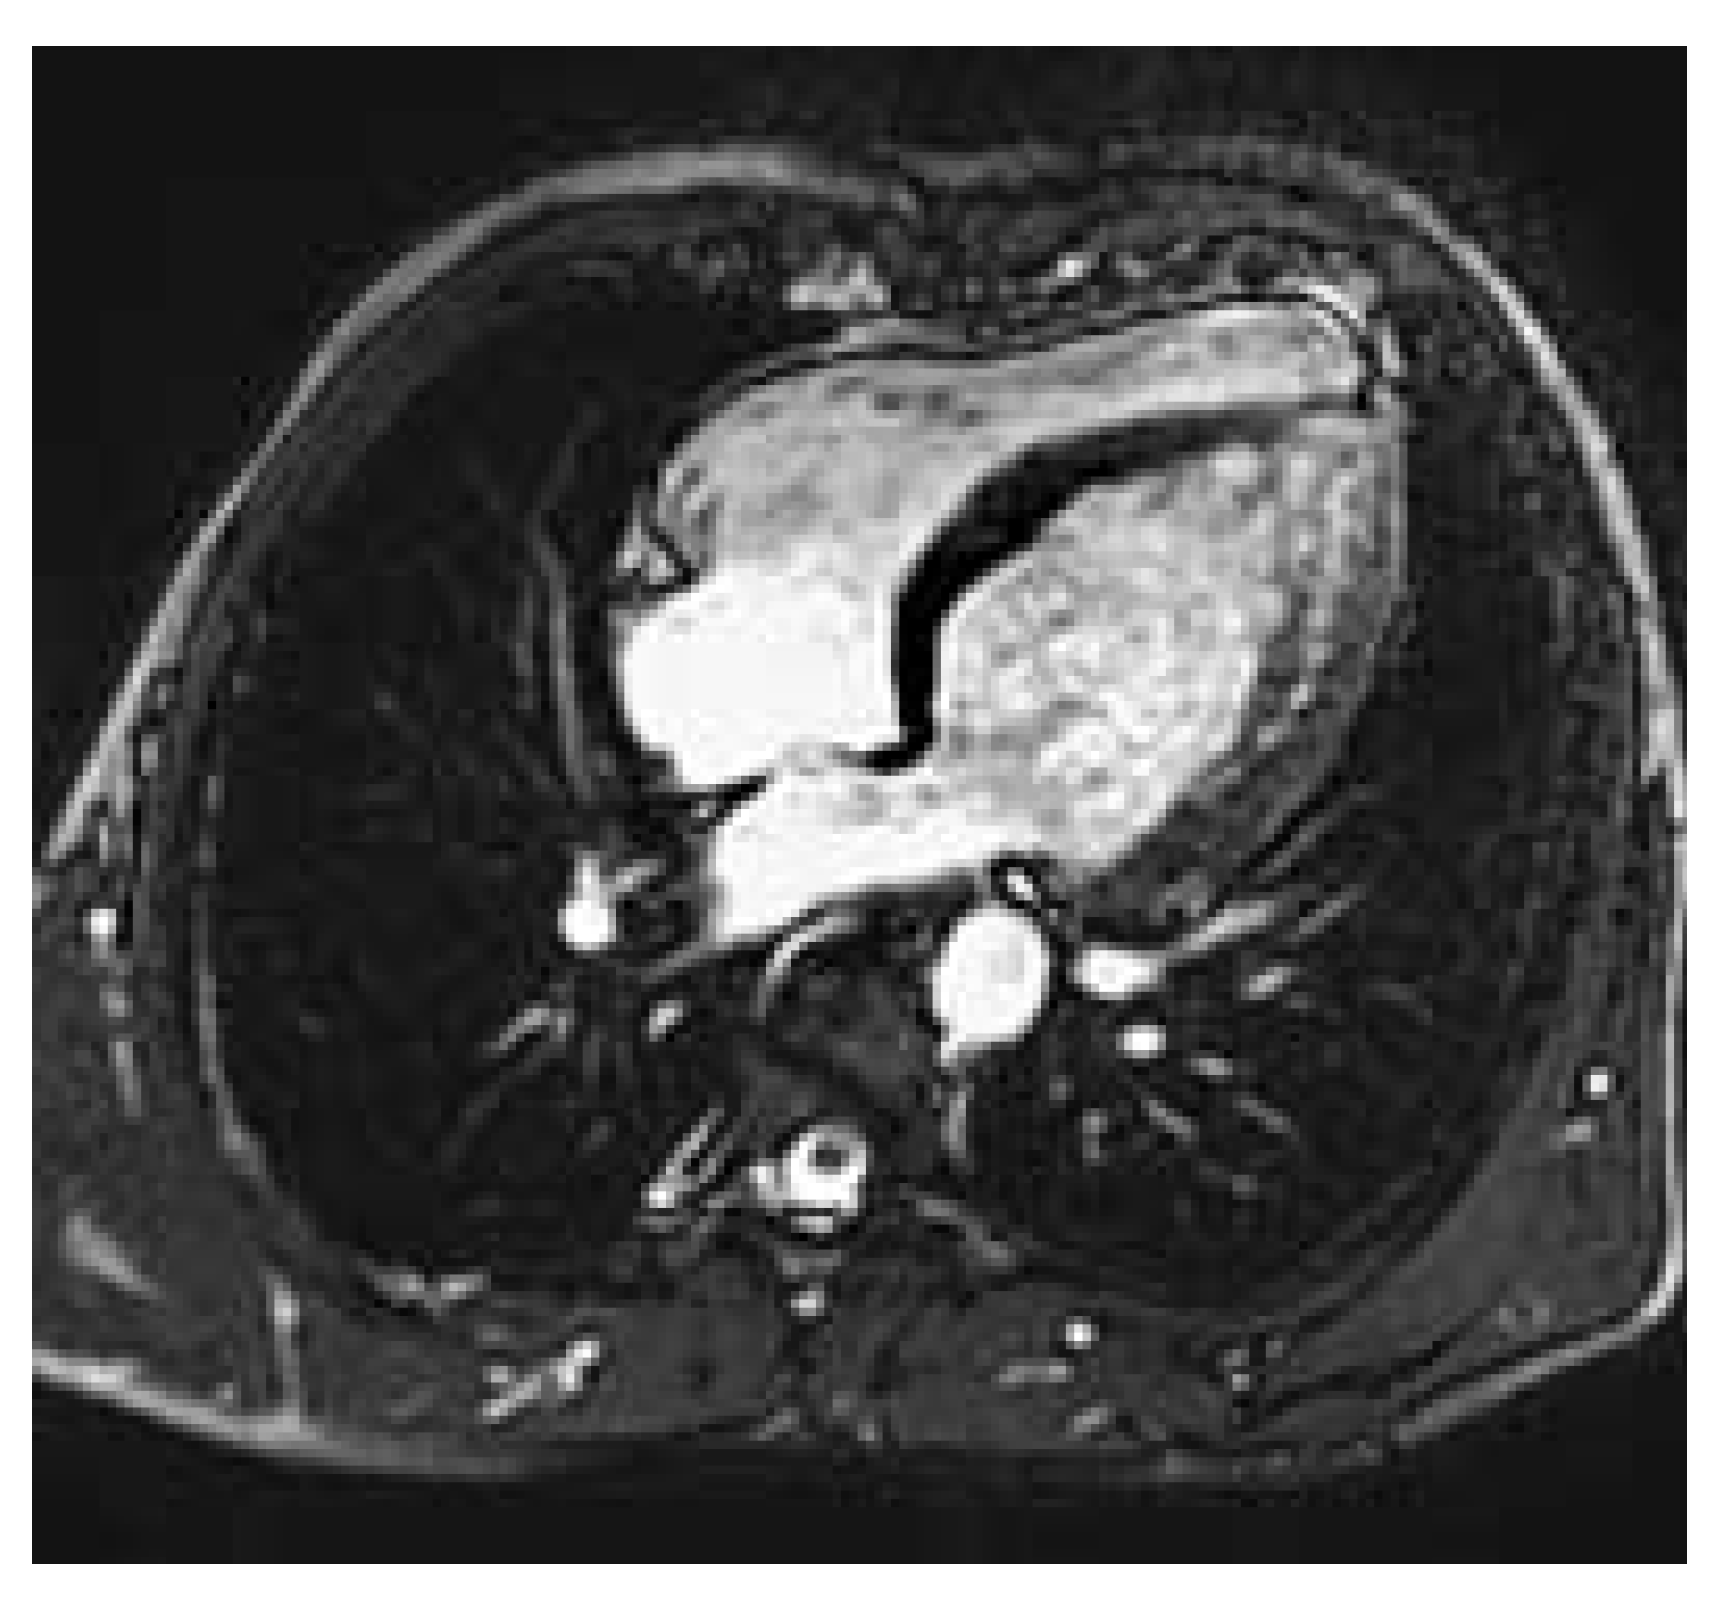

Figure 1. Left ventricle with apical thinning and apical / periapical trabeculations.

The chest radiograph showed no abnormality. The ECG at rest did not show left ventricular hypertrophy nor any other abnormality. However, on clinical examination, there was no palpable pulse in the lower extremities. The echocardiogram revealed the expected stenosis of the descending aorta with a peak gradient of 62 mm Hg. The left ventricle was not dilated (60 mm), but showed apical thinning (4.4 mm) and trabeculations with local hypokinesia. There was no valvular abnormality such as eg a bicuspid aortic valve, but a slight aortic root dilation (40 mm) was detected.

A cardiovascular magnetic resonance study (CMR) was performed at our institution in order to assess the exact location, the degree and severity of the aortic stenosis and to rule out associated congenital anomalies. CMR showed a normal left ventricular mass (181 g, 95.3 g/m2, [normal: 91 ± 11 g/m2]), a moderately reduced left ventricular ejection fraction of 37.6%, a diffuse, apically pronounced hypokinesia with apical trabeculations (fig. 1), and no late contrast enhancement. In CMR, the aortic root was slightly dilatated (40 mm), the ascending aorta was normal but the aortic arch was slightly hypoplastic. The proximal part of the descending aorta showed a severe postductal stenosis (fig. 2) of 28 mm in length, a small poststenotic saccular aneurysm (confirmed by surgery, fig. 3), and an extensive collateral vascular system through the subclavian, scapular, internal thoracic, and intercostal arteries. The origin and proximal course of the coronary arteries as well as the pulmonary venous return were normal.

In unusual presentation as in our case including virtual absence of symptoms, an only mild hypertension, a normal ECG at rest, and a normal chest radiograph, the diagnosis is difficult and can be easily missed. However, the absence of the pulse in the lower limbs reveals the “pulseless disease”. The additional findings in our patient included a left ventricular dysfunction, apical thinning and increased trabeculations, which may, however, also be due to an unknown coincidence with a form of cardiomyopathy, to hypertension, or due to an association of the coarctation with non compacted myocardium. This latter association has been published in a series of 12 patients with ventricular noncompaction [2].